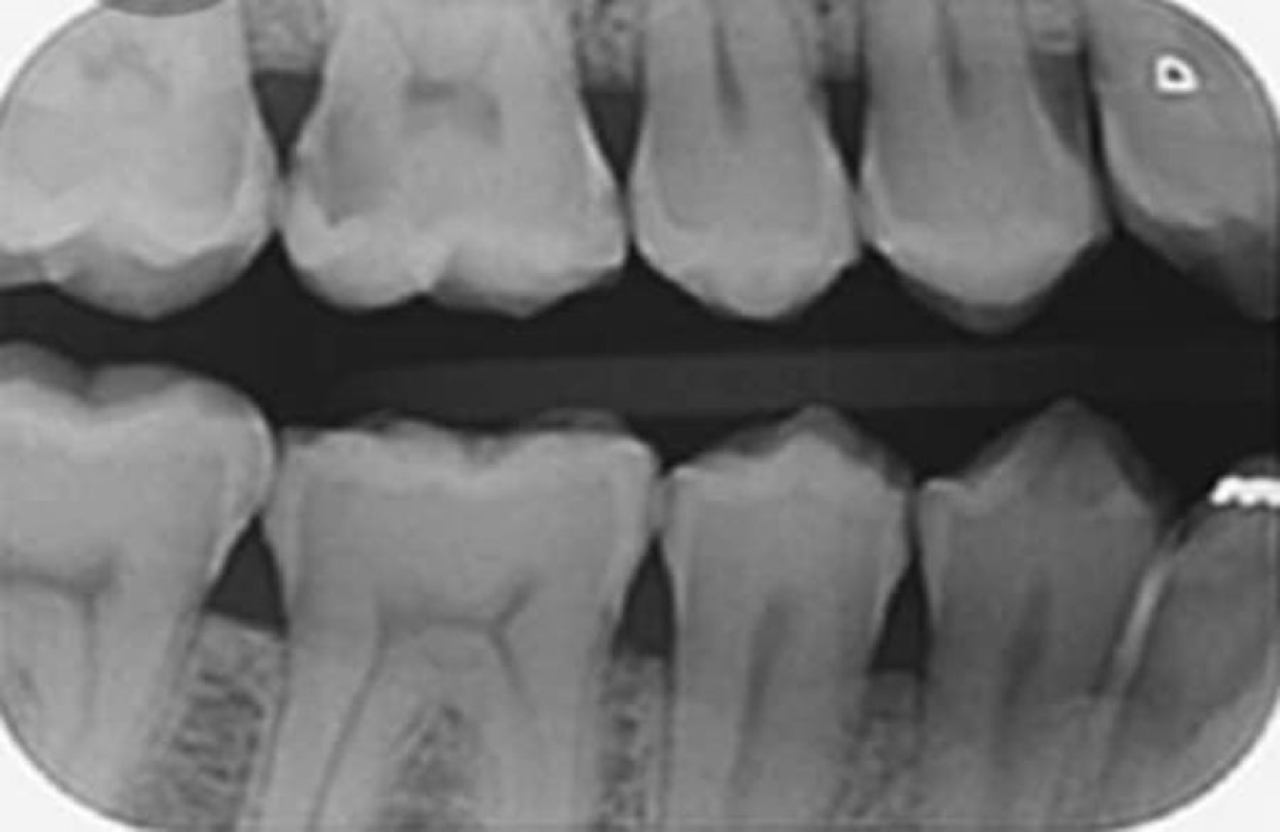

Dentalna dijagnostika

Marković Dental Clinic koristi najmoderniju rendgensku tehnologiju u dijagnostici orofacijalne regije.

Uz minimalnu dozu zračenja pacijenata i maksimalnu zaštitu, rendgenskim snimkama čeljusti možemo analizirati anatomske osobitosti zuba, čeljusti, patološke procese i tvorbe te visinu i širinu kosti čeljusti za planiranje dentalnih implantata.